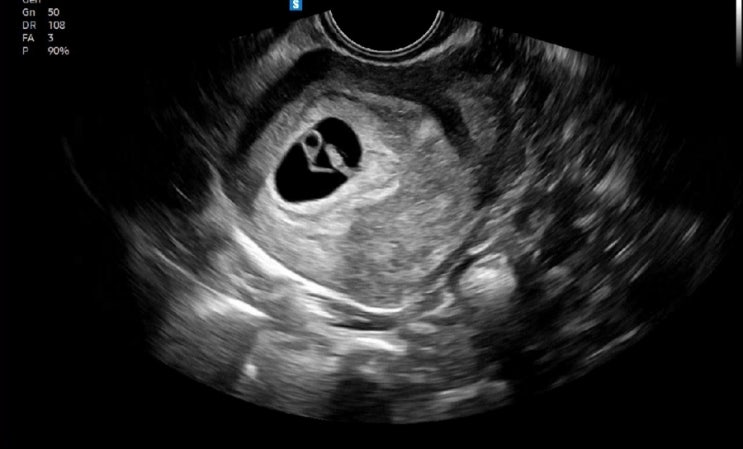

임신 9주차, 벌써 바우처 50남은거 실화임?.?

임신은...돈이었따.... 술을 안마셔서 긴축 가능할지도?!했찌만 ㅋㅋㅋㄲㅋㅋ 우선 9주1일차 진료를 보고왔...